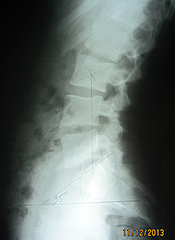

Lateral Lumbar

The lateral lumbar provides a wealth of information. Ferguson's gravity line is important, as it represents the athlete's center of gravity from the side. This marking originates in the center of L3, with a plumb line drawn straight downward. This line should bisect the anterior third of the sacral base. In Figure 7, we can see the line falls anterior to the norm. This finding produces increased stresses on the posterior structures of the spine, such as the pars and facets. Dr. Yochum has concluded that no one has ever been born with a pars defect, as pars defects are stress fractures that typically occur during adolescence. The incidence of pars defects increases with extension activities of the low back, as well as with an increased sacral base angle and an anterior Ferguson's gravity line.

Fig. 7: Anterior Ferguson's Line

In Figure 8, we see Ferguson's gravity line is posterior, suggesting the body's weight bearing is increased over the posterior disc and spinal nerve root. This increased stress, over time, will predictably increase disc injuries and nerve root irritations.